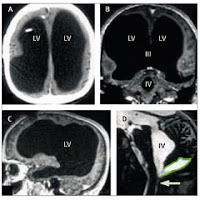

A ressonância magnética revelou "imagens muito invulgares, com cavidades ventriculares enormes", explicou o neurologista à AFP. "O cérebro em si, a substância cinzenta e a substância branca, estão comprimidas nas paredes do crânio".

Casado e pai de dois filhos, este francês de 44 anos, funcionário público, foi ao hospital em 2003, devido a um problema de locomoção. A equipa do doutor Lionel Feuillet diagnosticou uma hidrocefalia não comunicante, o que compreende um aumento da quantidade de líquido cefalorraquiano.